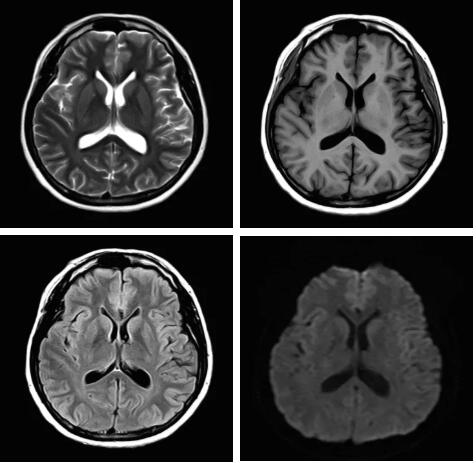

3.Pure射頻成像鏈

從成像源頭的磁體采用鍍膜新磁體高密度薄層鍍膜貼合技術(shù),獲得更好的磁場均勻度,奠定磁共振成像基礎(chǔ);采用3D RSCE微雕梯度精準(zhǔn)控制頻率和相位,輸出理想波形,實(shí)現(xiàn)渦流的“0”殘余,還原最真實(shí)的圖像信息;射頻接收端通過計(jì)算機(jī)人工智能對信號抗干擾處理,把信號放大并去除梯度、磁場等對信號干擾,再經(jīng)過二次人工智能信號識別,去除噪聲污染獲得純凈的信號;通過Pure射頻成像鏈的優(yōu)化和改進(jìn)使信噪比提升40%,這是磁共振領(lǐng)域革命性的顛覆和改變。

圖:Pure射頻成像鏈的優(yōu)化和改進(jìn)使信噪比提升